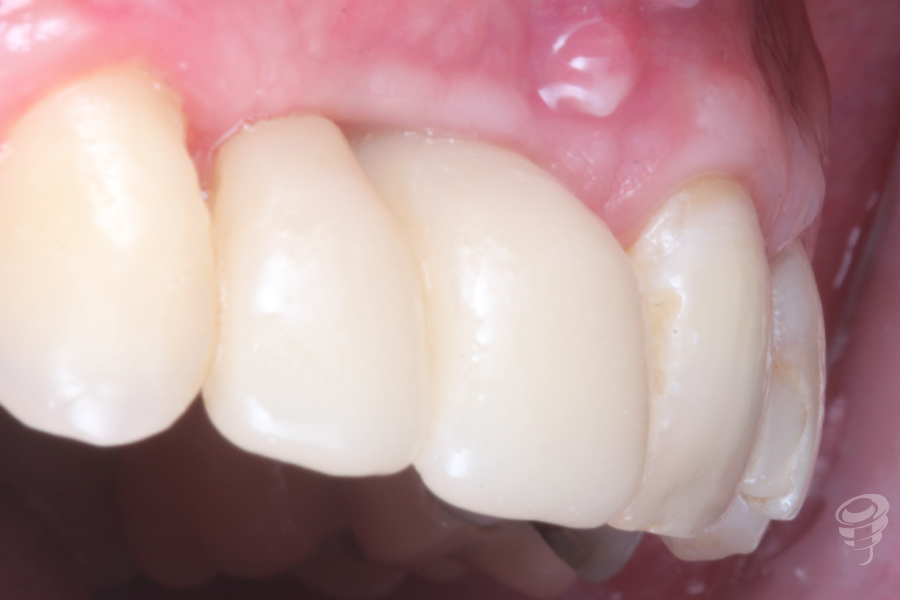

Resultado

Finalmente se puede observar un implante en una situación 3D adecuada y con un volumen de tejido duro y blando satisfactorio para conseguir unos buenos resultados estéticos y funcionales.

Imagen 15

Imagen 16